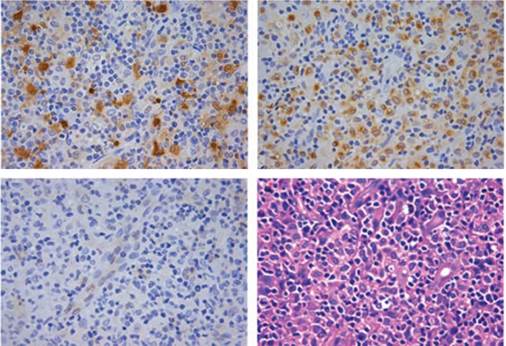

The histopathological study revealed histiocyte sheets at the frontal bone level with clear cytoplasm and rounded nuclei, without significant atypia, lymphocyte and neutrophil emperipolesis, positivity for CD68 and S100, and negativity for CD1a in immunohistochemistry (Figure 2). The microbiological study was negative for fungi, M. tuberculosis, atypical mycobacteria and Leishmania sp. These findings led to the diagnosis of extranodal Rosai-Dorfman disease with isolated bone involvement; an extension study was carried out, but no systemic affectation was detected.

Figure 2 The histopathological study showed histiocyte sheets with clear cytoplasm and rounded nuclei, without significant atypia and lymphocyte and neutrophil emperipolesis. Positivity for CD68 and S100 and negativity for CD1a were found in immunohistochemistry stains.